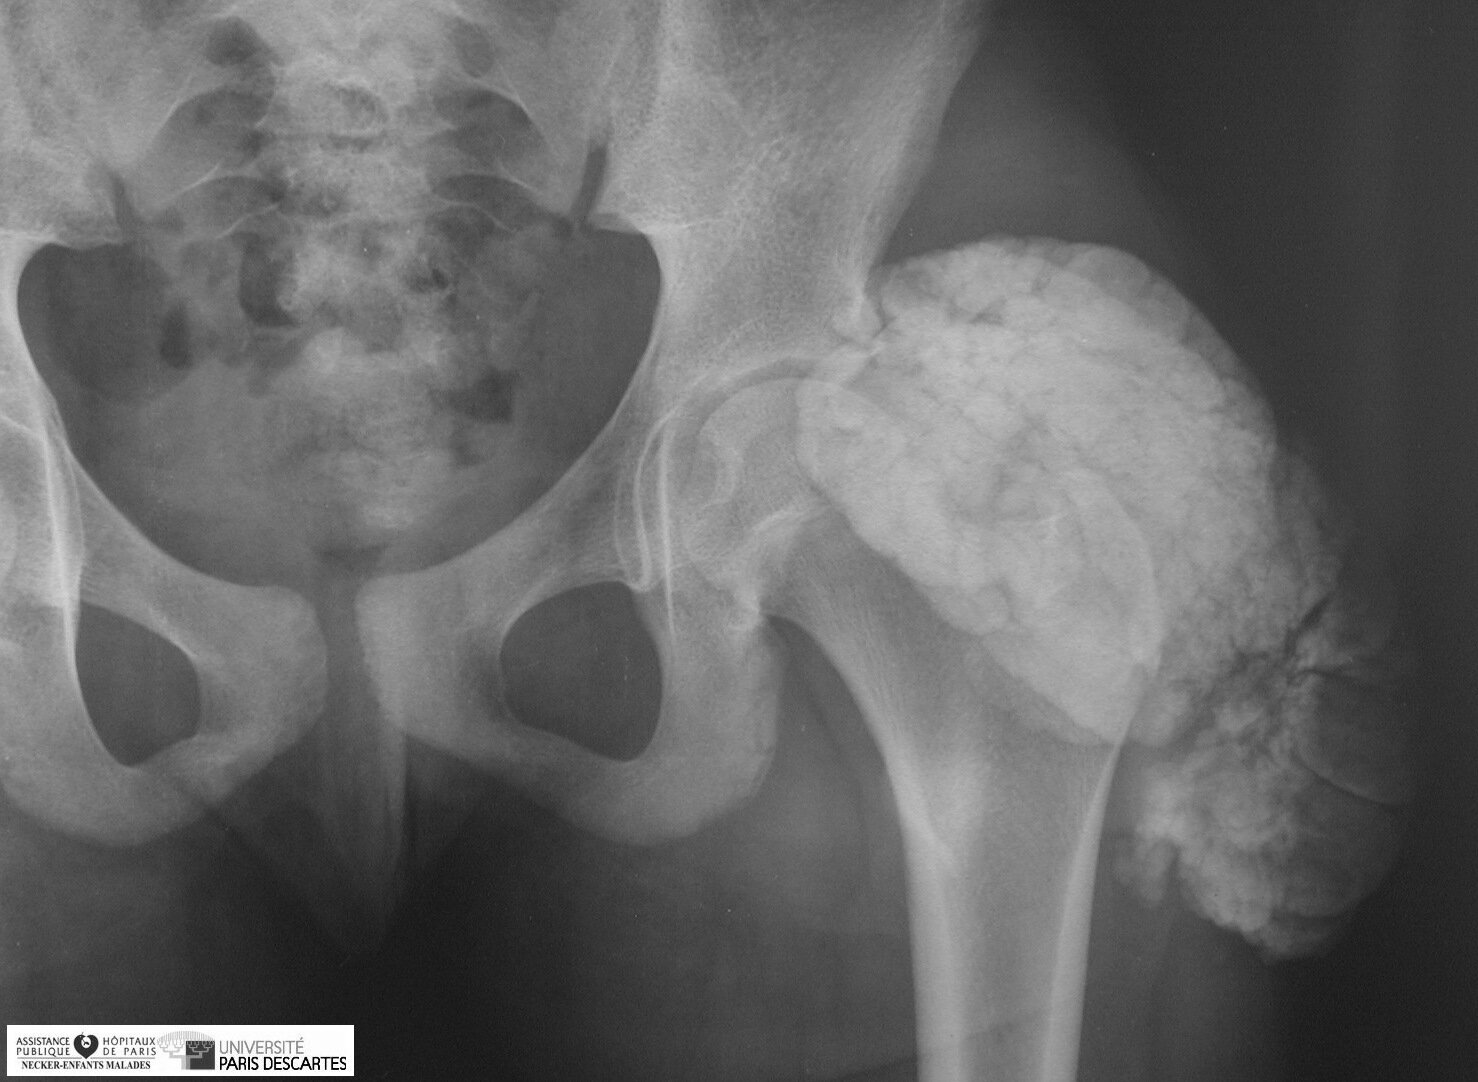

Tumoral Calcinosis